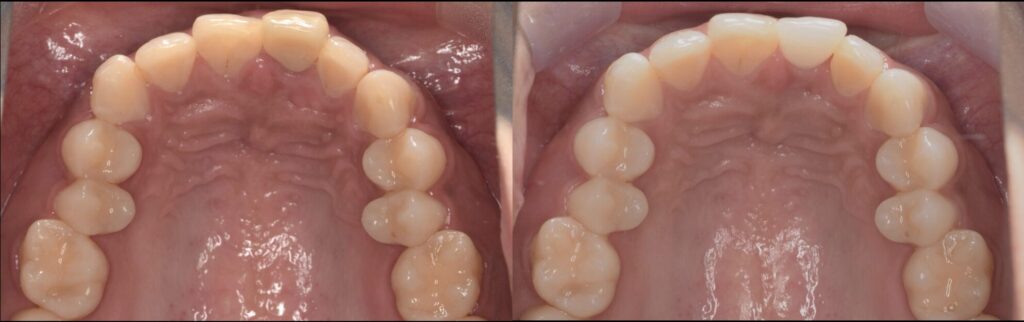

Before

After

初診時の口腔内写真とデンタルX線写真

インプラントSET後の口腔内写真とデンタルX線写真

インプラント埋入から2ヶ月半にて終了。